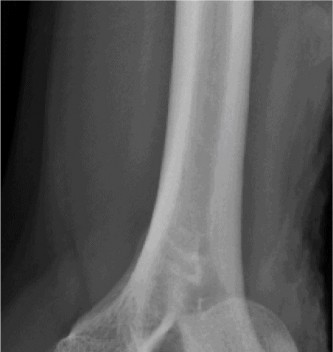

Understand common complications associated with performing surgery for scapulothoracic bursitis? CASE 33 A 42-year-old female presents to the office for follow up after sustaining a minimally displaced radial head fracture 3 months prior. She states she was initially treated in long-arm splint by the ER and did not follow up with an orthopaedic surgeon until now. Per her report, she removed the splint 4 weeks after the injury, but did not move her elbow due to pain. She now has no pain but is unable to reach that hand to her face or head. The remaining history is significant for previous ulnar nerve surgery for which she is unable to provide details. On physical examination, her upper extremity is normal except for limited flexion/extension, measured to be 80 to 50 degrees by goniometer. In addition, she has a well-healed surgical incision about the medial elbow, consistent with a previous surgery on her ulnar nerve. Her images are shown (Figs. 2–82 to 2–84).

Figure 2–82

Figure 2–83

Figure 2–84